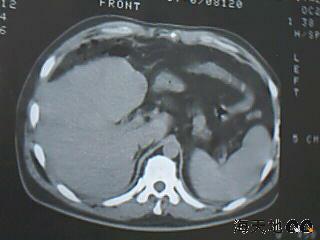

男 32y 外伤后一月余,现 t38.5,肝区隐痛。

右肝膈顶区液气平面.右膈肌增厚改变,病灶下部层面呈半月形延伸于肝表面.且于横结肠无明确密度切关系.

结合临床症状;考虑膈下脓肿.建议薄层矢状重建进一步证实.

鉴别;1,膈疝;2,间位结肠.

右隔肌与肝顶之间隙有长气液平,其下散在点状气体影,右侧腹膜局限增厚。考虑右膈下脓肿。

考虑右膈下脓肿。病灶不在肝内,位于肝外膈下;病灶下方的层面无结肠影与之相连。

右膈肌增厚,肝膈间见条状低密度影内可见积气影及宽大液平面,并未见与结肠相连。因此考虑膈下脓肿。